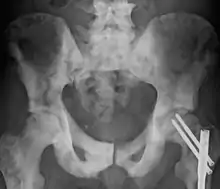

Sclerosis of the bones of the pelvis due to prostate cancer metastases

Osteosclerosis is a disorder that is characterized by abnormal hardening of bone and an elevation in bone density. It may predominantly affect the medullary portion and/or cortex of bone. Plain radiographs are a valuable tool for detecting and classifying osteosclerotic disorders.[1][2] It can manifest in localized or generalized osteosclerosis. Localized osteosclerosis can be caused by Legg–Calvé–Perthes disease, sickle-cell disease and osteoarthritis among others. Osteosclerosis can be classified in accordance with the causative factor into acquired and hereditary.[2][1]

Diagnosis

Osteosclerosis can be detected with a simple radiography. There are white portions of the bone which appear due to the increased number of bone trabeculae.